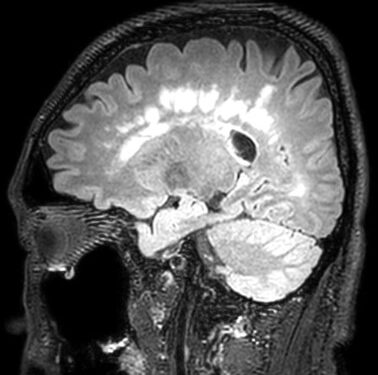

Информация о диссеминированном рассеянном энцефаломиелите